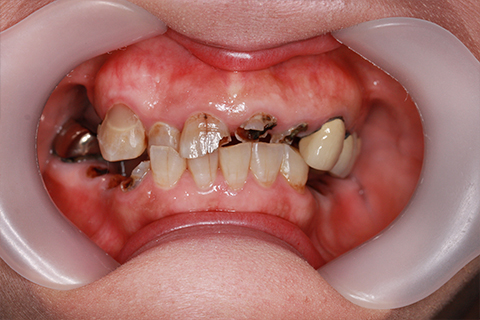

治療前

治療後

- 年齢・性別

- 60歳

- 治療期間

- 6ヶ月

- 抜歯

- 残根抜歯のみ

- 治療費

- 184.8万円

- 備考

- 右上5.6 右下5 左下4.5.6欠損

- 治療内容

- 6本のインプラントを右左側に2回に分けて埋入

- 施術の副作用(リスク)

- オペによる知覚障害。インプラントによる歯肉炎。インプラント脱落。